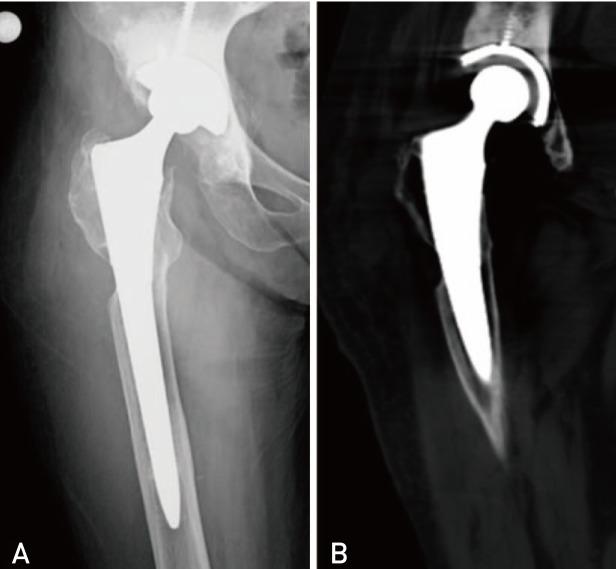

Periprosthetic joint infection (PJI) due to is rare. It frequently occurs patients receiving immunosuppressive medicine. We describe two periprosthetic infection of two immunocompromised patients. Both of patients were receiving azathioprine and prednisolone therapy. First patient presented six years after total hip arthroplasty with a huge abscess on her right thigh that was reached to femoral component through the lytic area of lateral femur. Second patient presented with drainage from his hip and he had undergone two-step revision surgery for PJI 3 months ago. There is no consensus in the treatment of periprosthetic salmonella infections. We prefer two-step revision surgery for these infections as previously described in the literature.